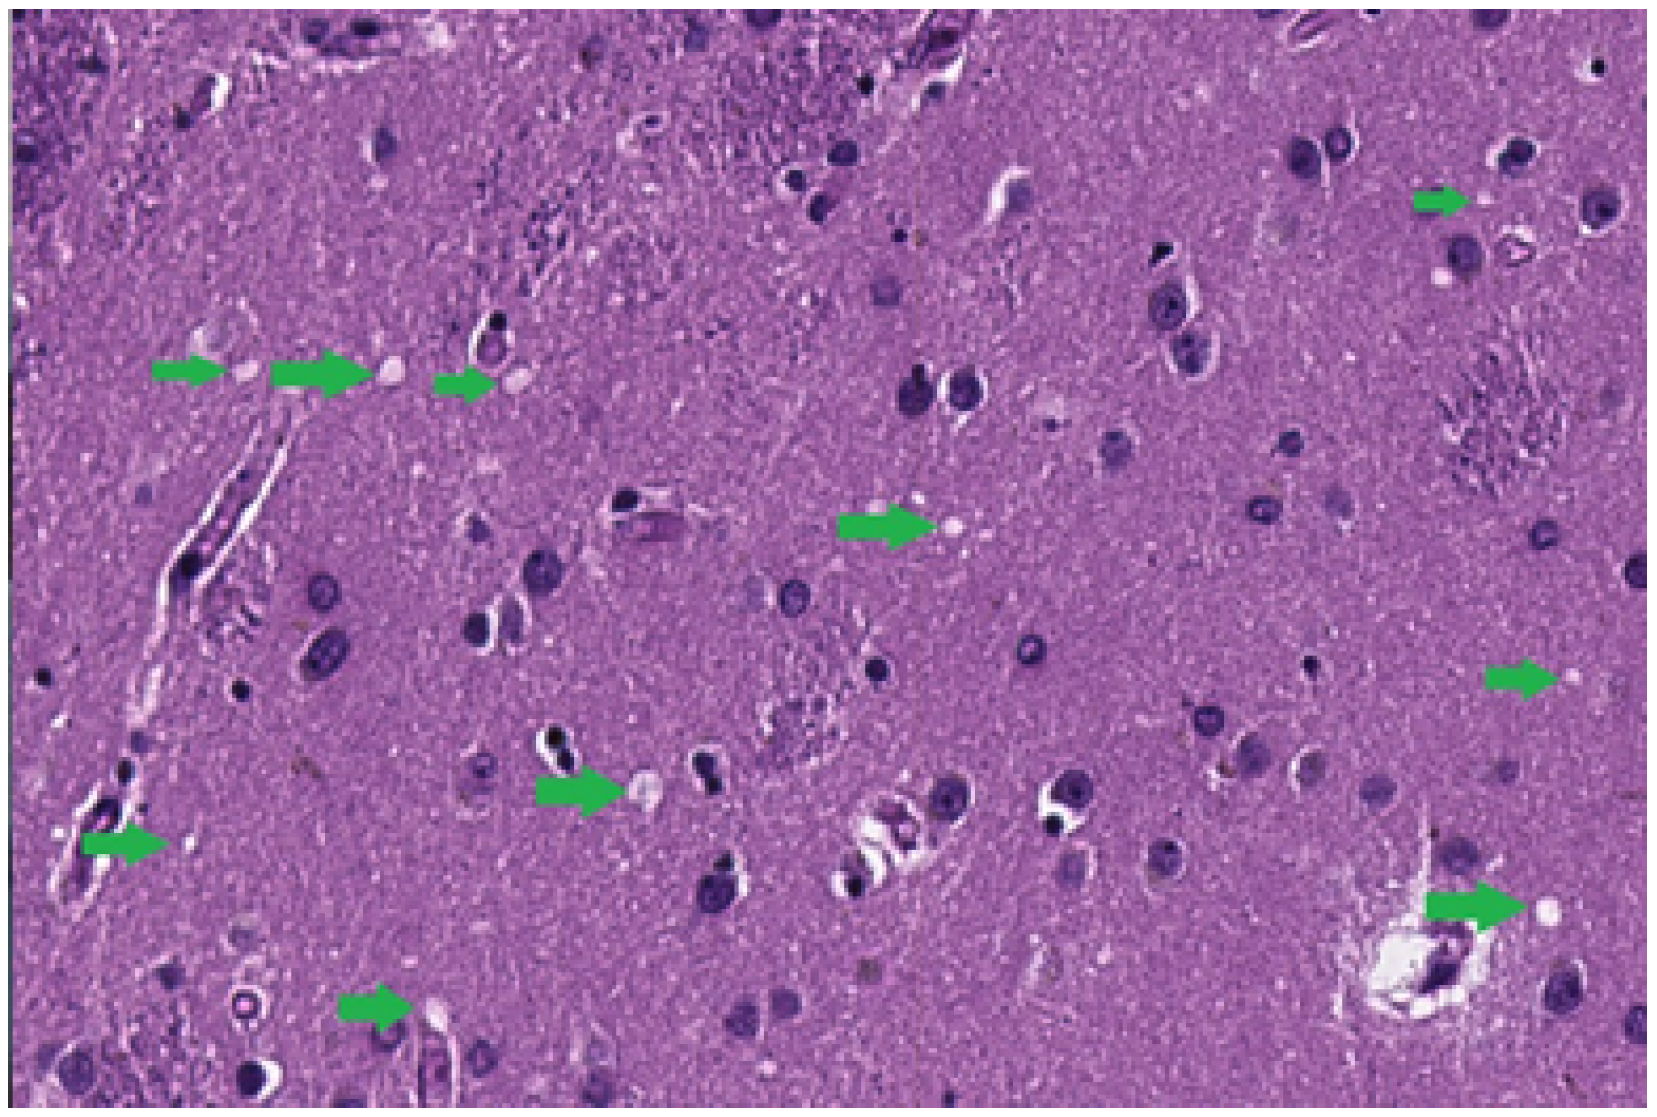

4.1. Spongiosis Segmentation